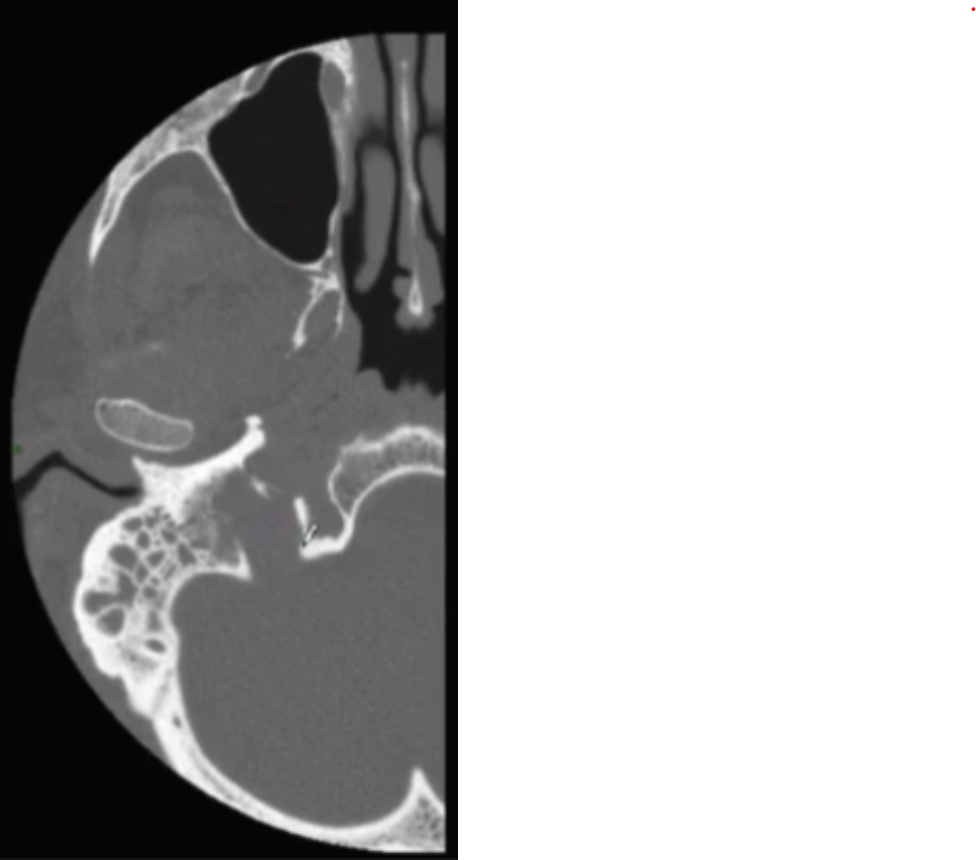

Absent Vertical Carotid Canal

• So basically carotid artery has to come straight up from neck to the brain obviously

• If your are missing the vertical portion in the carotid canal it will look like this where you have this soft tissue density looking thing horizontally oriented

• Also notice vs the normal the lack of the vertically oriented part of the carotid canal

• Do not biopsy - common question

• Happens because there is regression of the cervical carotid artery and will have enlargement of the collaterals that are through the middle ear